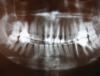

pawa Опубликовано 9 февраля, 2011 Поделиться Опубликовано 9 февраля, 2011 спасибо за ответ!я тоже склоняюсь ко вкладкам из циркония, единственное , что смущает, как говорят, они раз и навсегда...но без вкладок никак , да?и еще, если каналы запломбированы хорошо (по словам нескольких врачей), то их перелечивать необязательно? почему-то никто из тех, у кого я была об этом ничего не говорил и на мой вопрос отвечали:что это не обязательно.без вкладок никак.Если хорошо запломбированы то не надо. По этому снимку 100процентно сказать о качестве пломбировки нельзя. Ссылка на комментарий

pawa Опубликовано 9 февраля, 2011 Поделиться Опубликовано 9 февраля, 2011 (изменено) читайте внимательнеепрозрачный намёкhttp://s59.radikal.ru/i163/1102/ec/d15e3c4ab1ac.jpg один из моих передних точно депульпированный и поменял цвет.как же тогда с ним быть?Все четыре Ваших резца депульпированы. Изменено 9 февраля, 2011 пользователем pawa Ссылка на комментарий

sedoimd Опубликовано 9 февраля, 2011 Поделиться Опубликовано 9 февраля, 2011 один из моих передних точно депульпированный и поменял цвет.как же тогда с ним быть?судя по вашему снимку у вас депульпированны все 4 резца на верхней челюсти но потемнел только один соответственно:если выбираем терапевтическое лечение путем эсстетических рестовраций1)отбеливаем все зубы и по полученному результату меняем цвет потемневшего зуба и остальных резцов путём востоновления фотополимерными пломбировачными материаломи (на сегоднешний день есть всевозможные цвета)2)если цвет "остальных"зубов устраивает меняем цвет потемневшего зуба путём востоновления фотополимерными пломбировачными материаломи (на сегоднешний день есть всевозможные цвета) Ссылка на комментарий